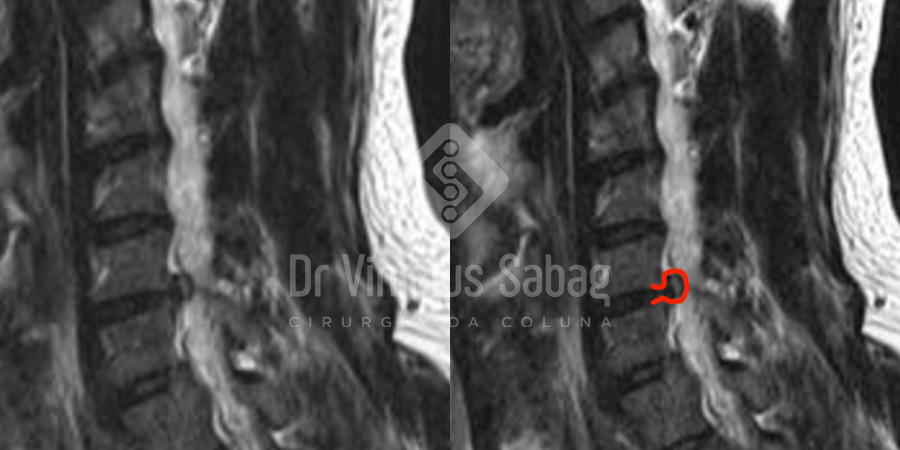

Diante da persistência da dor, foi solicitada uma ressonância magnética da coluna cervical para melhor investigação diagnóstica. O exame evidenciou a presença de uma hérnia discal extrusa ao nível de C6-C7, com compressão da raiz nervosa correspondente ao membro superior esquerdo, justificando plenamente o quadro clínico apresentado.

Ressonância magnética evidenciando hérnia discal extrusa em C6-C7 com compressão dos nervos.